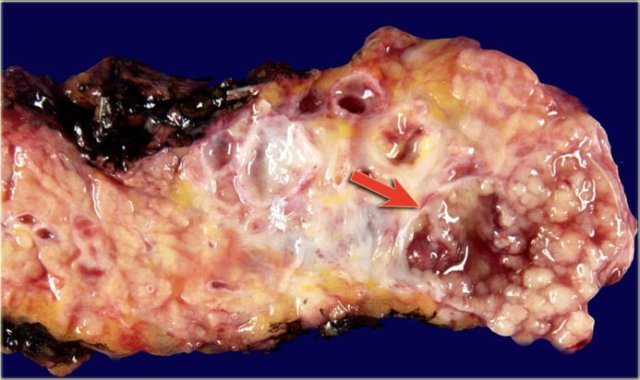

The pathology specimen shows multiple microcysts, which gives the tumor a lobulated appearance.

The pathology specimen shows a cystic tumor with multiple small cysts and a central scar.

There are no calcifications.

Macroscopic specimen of a IPMN showing mucinous tumor, with extensive mucin producing papilary neoplasm (arrow).